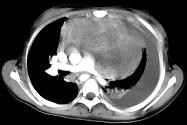

患者胸痛胸闷,CT如图,最可能的诊断为 ( )A.良性胸腺瘤B.恶性畸胎瘤C.侵袭性胸腺瘤D.表皮样囊肿E.淋巴瘤

问题 患者胸痛胸闷,CT如图,最可能的诊断为 ( )

选项 A.良性胸腺瘤 B.恶性畸胎瘤 C.侵袭性胸腺瘤 D.表皮样囊肿 E.淋巴瘤

答案 D